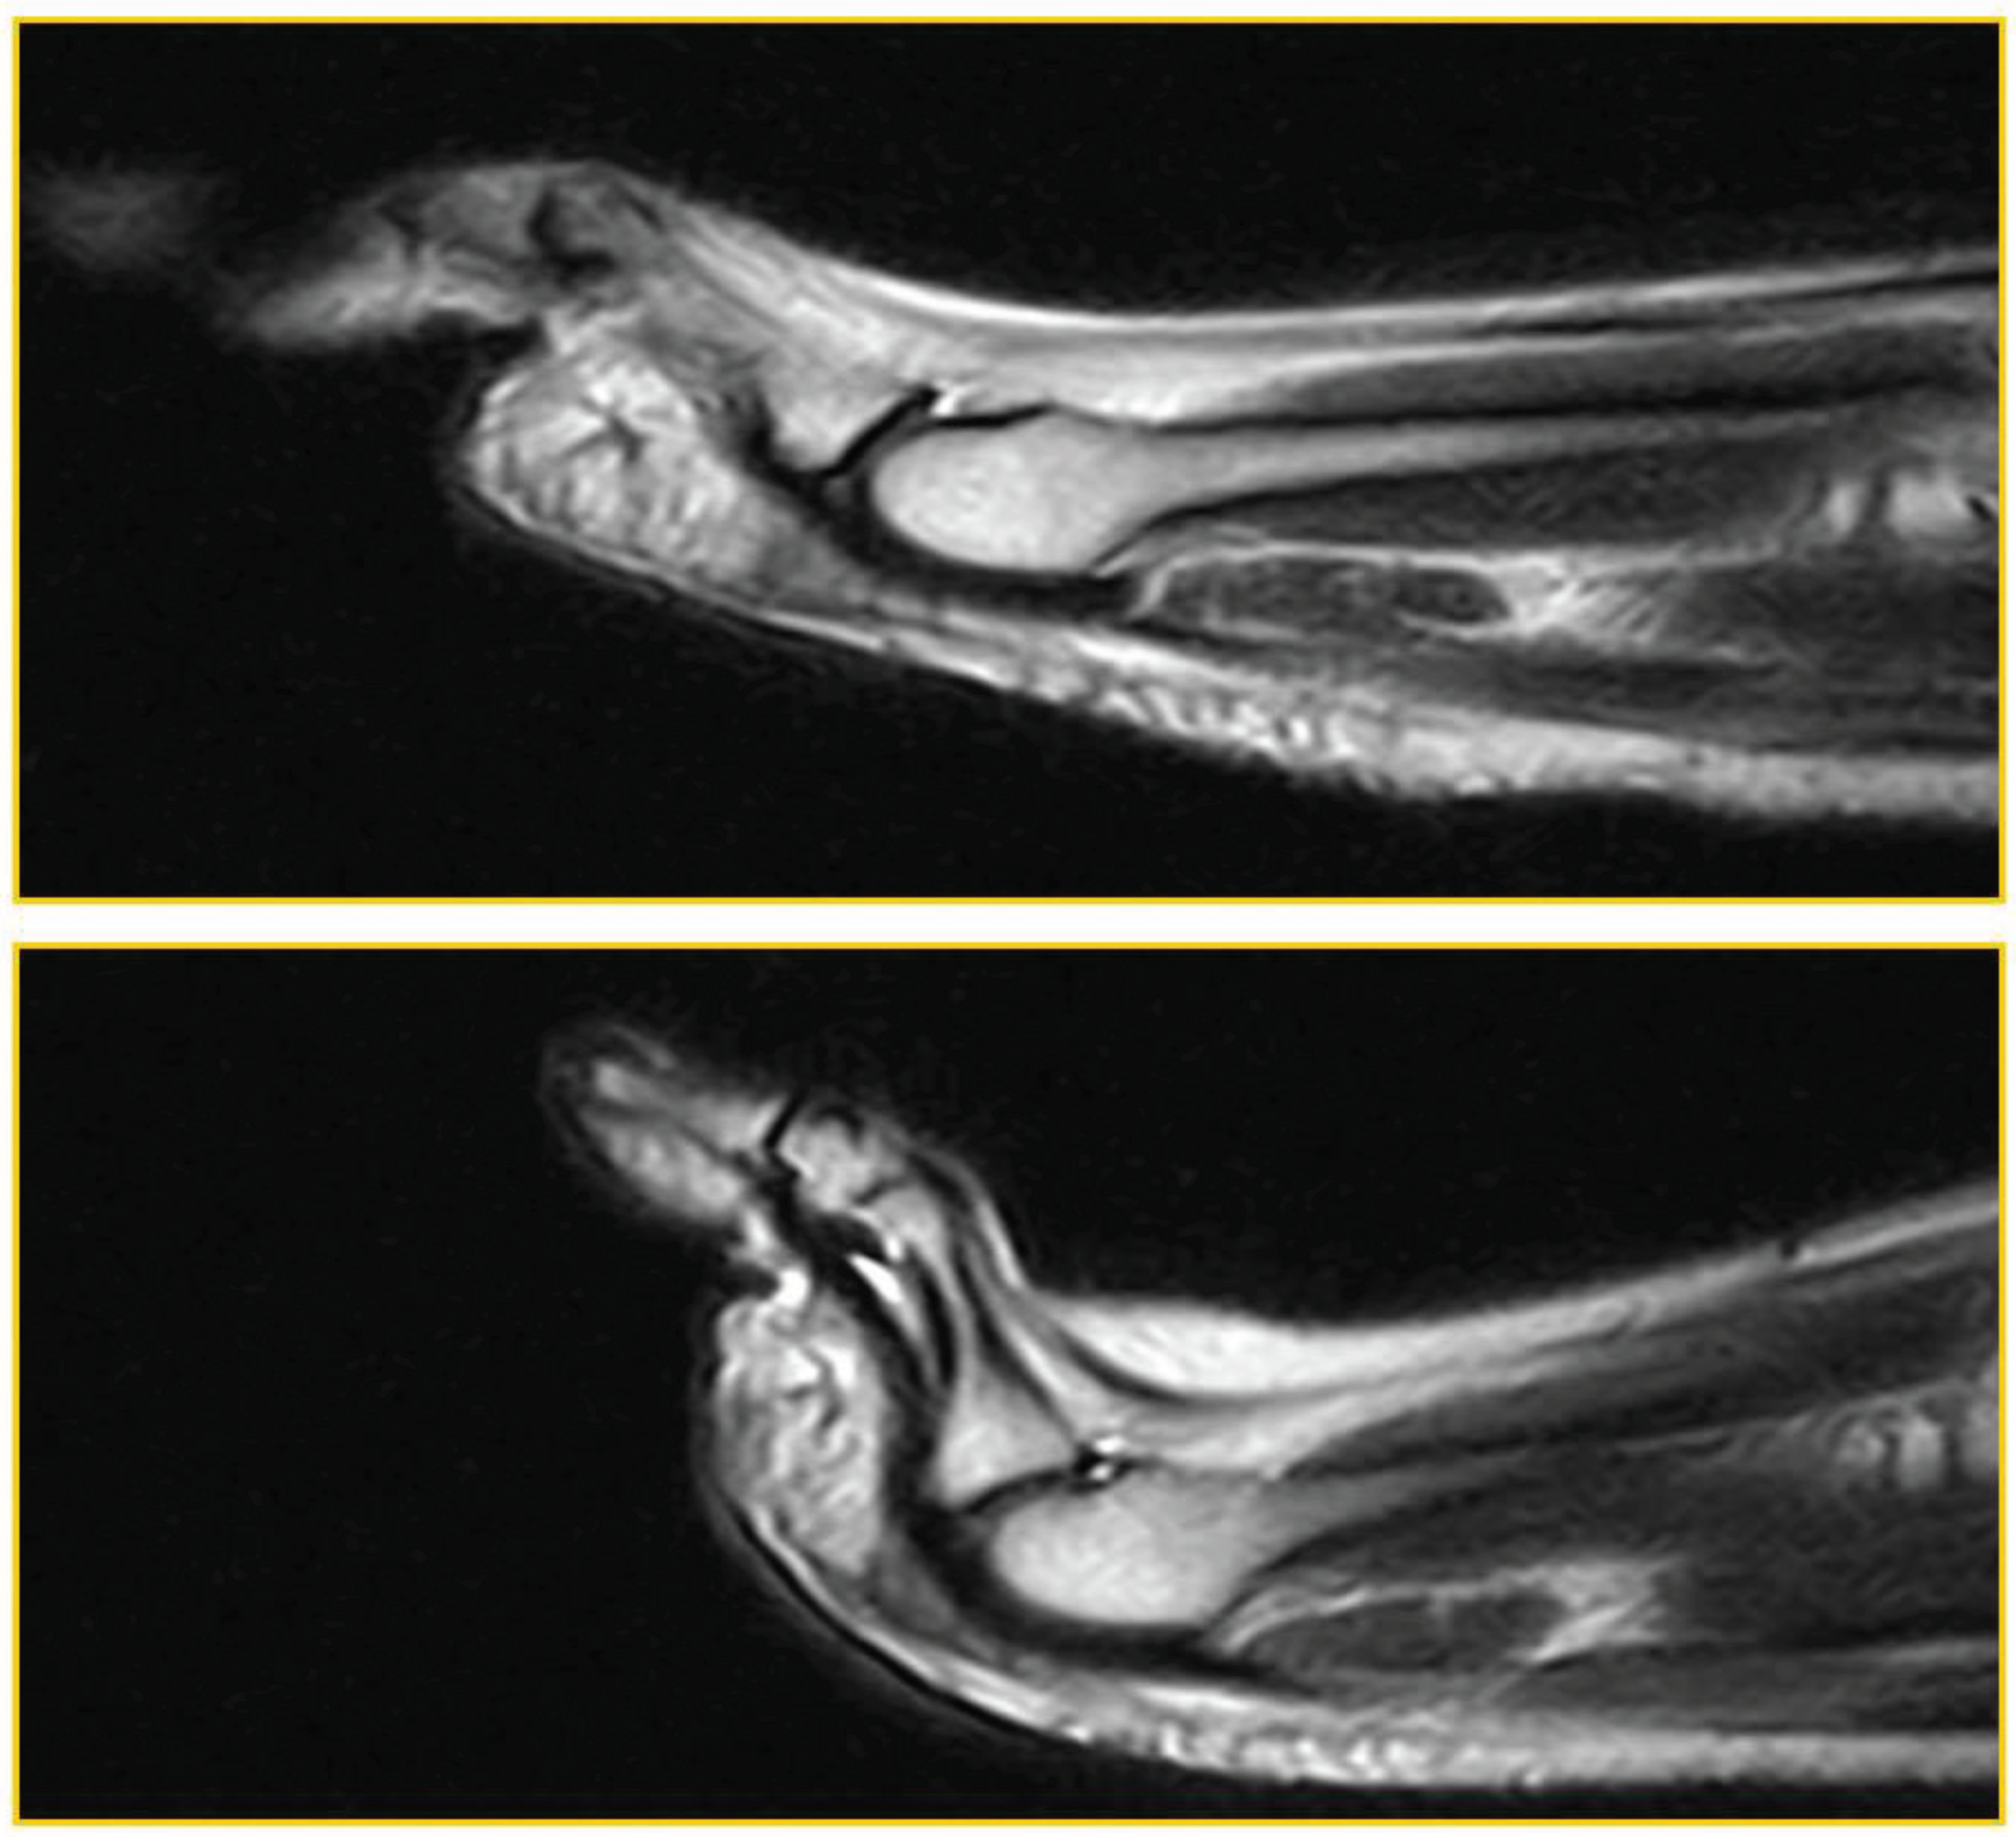

Figure 1. standard position with joint hyperextension , “stress test”.

In this figure, first on the left is the standard execution of the examination, with the foot in a neutral position, then the stress test is shown, in which a forced hyperextension of the toes is achieved, placing the plantar plate itself in traction.

A 45-degree dorsiflexion stress test was then performed for approximately 2.30 minutes, the time required for completion of the sequence. No further diagnostic investigations were necessary; no patients underwent arthrography or arthro-MRI.